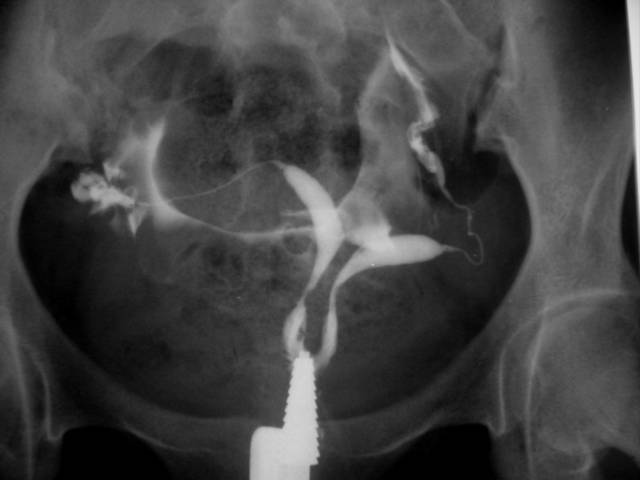

Η υστεροσαλπιγγογραφία είναι στην ουσία μια ακτινογραφία της μήτρας και των σαλπίγγων. Πραγματοποιείται προκειμένου να διαπιστωθεί αν οι σάλπιγγες μιας γυναίκας είναι διαβατές και αν η κοιλότητα της μήτρας είναι φυσιολογική.

Προκειμένου να αποτυπωθεί η εικόνα των σαλπίγγων και της μήτρας εκχύνεται στη μήτρα της γυναίκας ειδική σκιαγραφική ουσία. Η σκιαγραφική ουσία από τη μήτρα προχωρά προς τις σάλπιγγες και όλη πορεία παρατηρείται μέσω μιας οθόνης ακτινοσκοπήσεων. Έτσι φαίνεται ξεκάθαρα κατά πόσο οι σάλπιγγες είναι διαβατές ή αν έχουν υποστεί ζημιά. Επίσης, φαίνεται το σχήμα της μήτρας και η παρουσία ανωμαλιών της διάπλασης (διάφραγμα, συμφύσεις, ινομυώματα), οι οποίες μπορεί να προκαλέσουν υπογονιμότητα ή αποβολές. Η υστεροσαλπιγγογραφία δεν είναι κατάλληλη εξέταση για την κατάσταση των ωοθηκών ή για τη διάγνωση της ενδομητρίωσης.Η καλύτερη χρονική στιγμή για την εξέταση είναι οι 10 πρώτες μέρες του κύκλου (αλλά αφού έχει σταματήσει η αιμορραγία), προκειμένου να αποφύγουμε το ενδεχόμενο να είναι η γυναίκα έγκυος όταν κάνει την εξέταση.